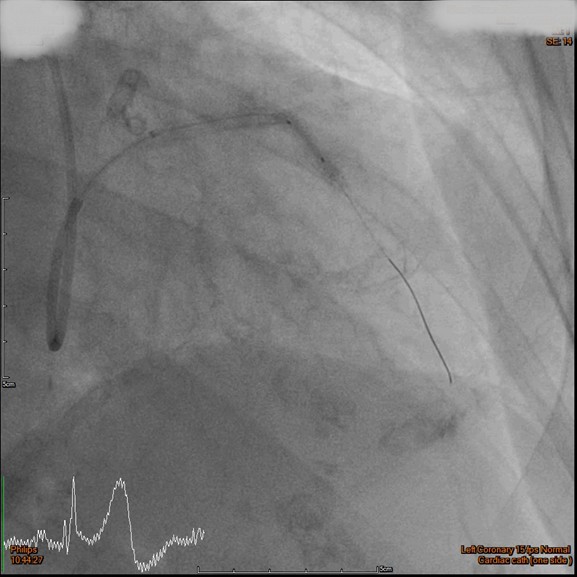

The RCA was calcified but no significantly severe stenosis.The LCX was calcified with mild stenotic lesion and a patent old stent.The LAD was severely calcified with an under-expanded old stent at middle to distal part. The lesion was also severely stenotic. The proximal to middle LAD had moderately stenotic lesion with calcification also.

Initially, we tried to insert IVUS catheter but unable to cross the lesion. We tried a NC balloon but unable to cross it also.Hence, we used rotational atherectomy with 1.5mm burr. However, the burr was unable to cross lesion even in high speed and entrapped in the stent.We removed the burr in guide extension catheter then the NC balloon could cross the lesion. The IVUS cather could also cross it with guide extension catheter support. The stent was almost not expanded. We tried NC balloon high pressure dilation but balloon slippage and burst. The lesion was still un-dilatable. We insert cutting balloon which avoided slippage but remained burst. We escalated the burr size to 1.75mm. The larger burr was not stucked but still unable to cross lesion. Besides, the larger burr causing slow blood flow. After adenosine injection, the patient's blood flow recovered. We reduced the burred size to 1.25mm which cross the lesion once but entrapped while doing polishment. After burr retrieval, we used NC balloon high pressure dilation. The balloon bursted but the lesion remained un-dilatable.Finally, the lithotrypsy balloon could cross the lesion and eliminate 80 pulses. The lesion was expanded much well. The IVUS showed the old stent was expanded and calcium was cracked. We deployed a new stent for old one destruction and proximal dissection. The final IVUS image showed epansion and apposition were accpetable.